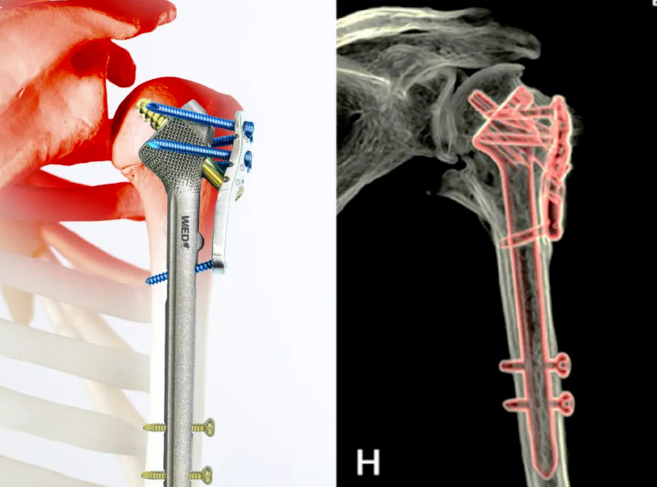

图片

图1 患者术前X-ray